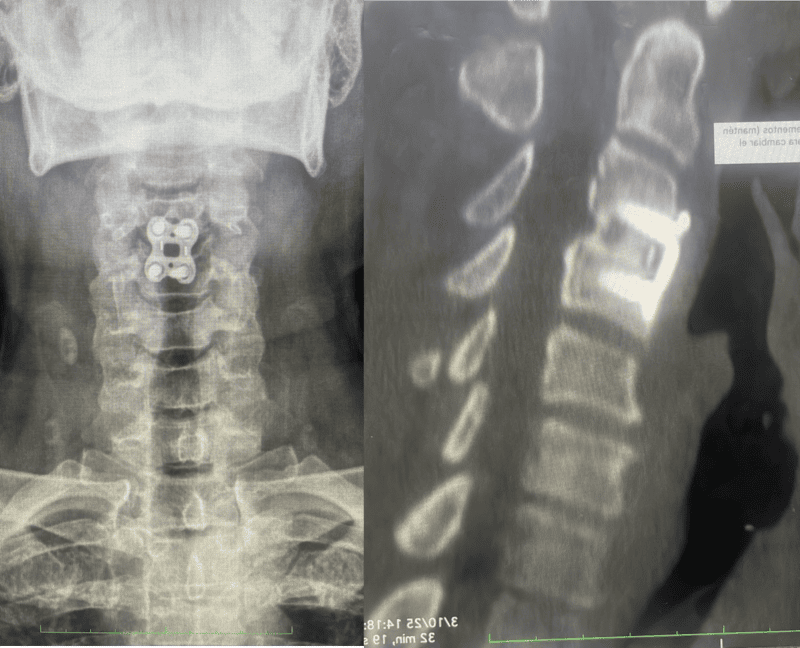

¿Cómo diagnosticarla? A través de exámenes de imagen como Resonancia Magnética Nuclear (RMN) es la más utilizada y efectiva para el diagnóstico de la hernia de disco cervical, ofrece imágenes de alta resolución de las partes blandas (disco, hernia, nervios). La Tomografía Computarizada (TC) también puede ser útil para evaluar la parte ósea. Los estudios radiográficos de proyección dinámica son importantes para valorar la estabilidad del segmento afectado (espondilolistesis).

Tratamiento: Inicialmente, el tratamiento conservador incluye analgésicos, antiinflamatorios, relajantes musculares y fármacos neurolépticos. Estos deben combinarse con fisioterapia, ejercicio y cambios en hábitos diarios perjudiciales (como levantar objetos pesados o mantener malas posturas). Si tras uno o dos meses no se obtienen resultados o los síntomas empeoran, en Ortho Spine Center valoramos otros procedimientos de mínima invasión o quirúrgicos para reducir los episodios de dolor.

En casos de reproducción de la hernia, hernias de base ancha con compresión radicular bilateral o asociadas a otras patologías que lo requieran, se plantea una cirugía instrumentada. Esta puede ser una artroplastia discal (ADR) (reemplazo del disco dañado por uno artificial) o, en casos con elementos anatómicos adicionales dañados, una artrodesis o fusión.